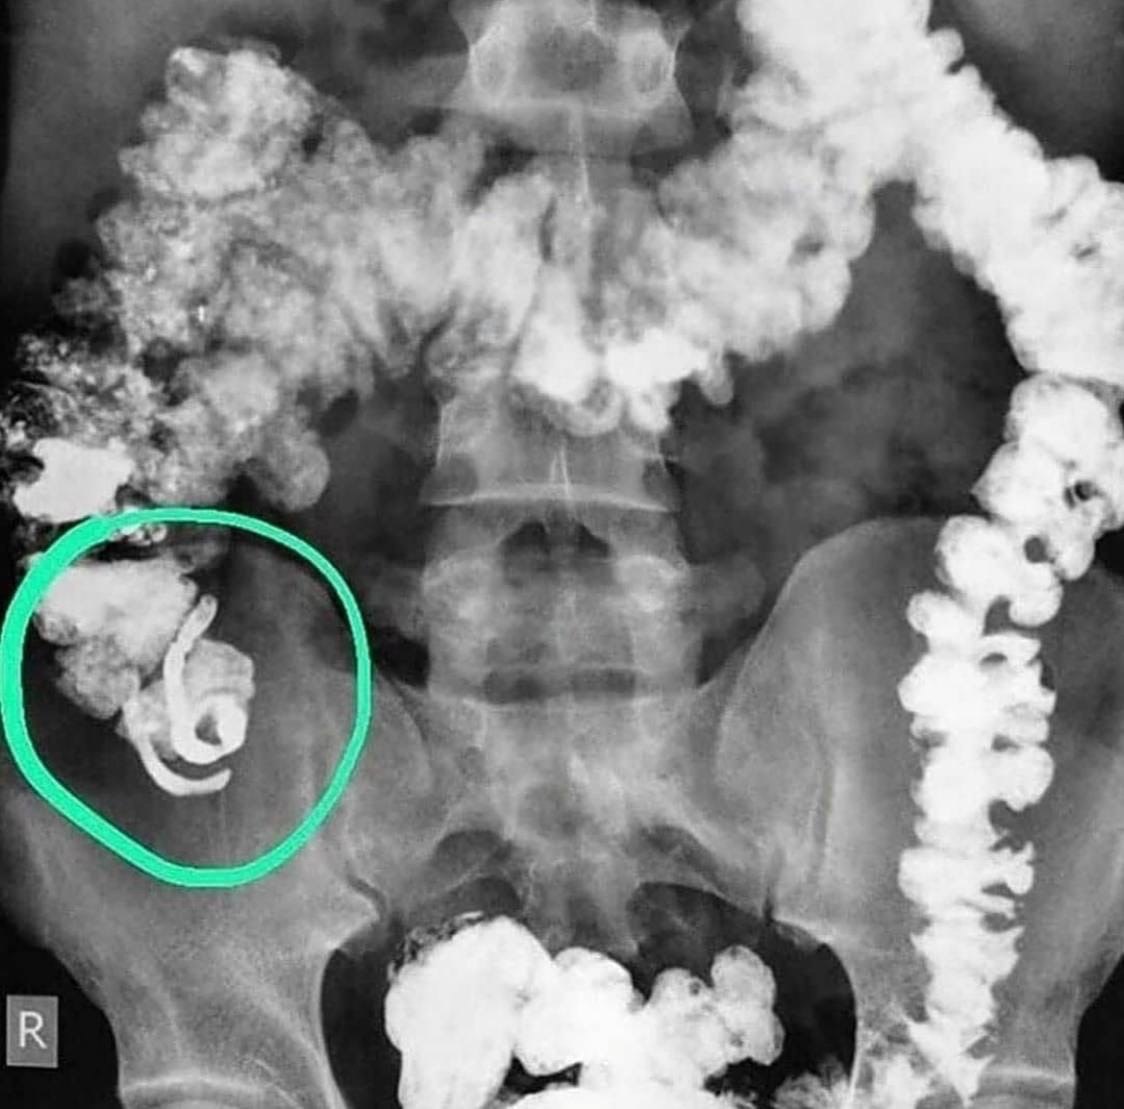

A contrast study of the patient's intestines revealed a very rare anomaly - a double appendix. This happens extremely rarely: 1 case in 25,000. . . . . #DoubleAppendix #RareAnomaly #MedicalMystery #AppendixHealth #Gastrointestinal #HealthAwareness #RareDiseases #MedicalResearch